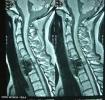

Lesión MedularEl Lokomat, un nuevo aparato de neurorrehabilitación, reproduce de forma óptima la marcha fisiológica del paciente con lesión medular, se adapta a su deficiencia y le ofrece una rehabilitación más rápida y mejor.

El Instituto Guttmann, centro especializado en neurorrehabilitación, ha sido el primero de España en incorporar en sus instalaciones el Lokomat, un ingenio mecánico que permite acelerar la rehabilitación de los pacientes que han sufrido una lesión medular incompleta.